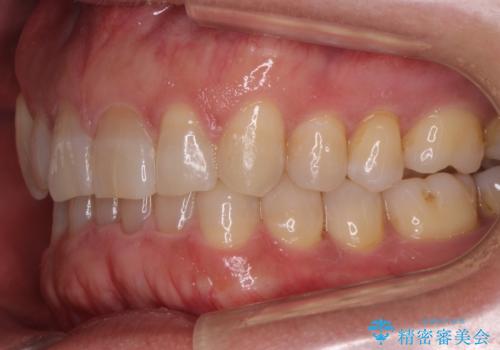

八重歯と下の歯のがたつき マウスピースで

- 右上の犬歯が目立つのが気になる、下の歯並びも治したいとのことで来院。

歯を抜かずに少し削って小さくして並べました。

並びも良くなり、患者様にも喜んでいただきました。

右上の犬歯の歯肉退縮自体は進行する可能性をお伝えしておりましたが、特に変化なく治療できました。

歯肉退縮につきましては、歯ぐきの移植を提案しましたが特に希望されませんでした。